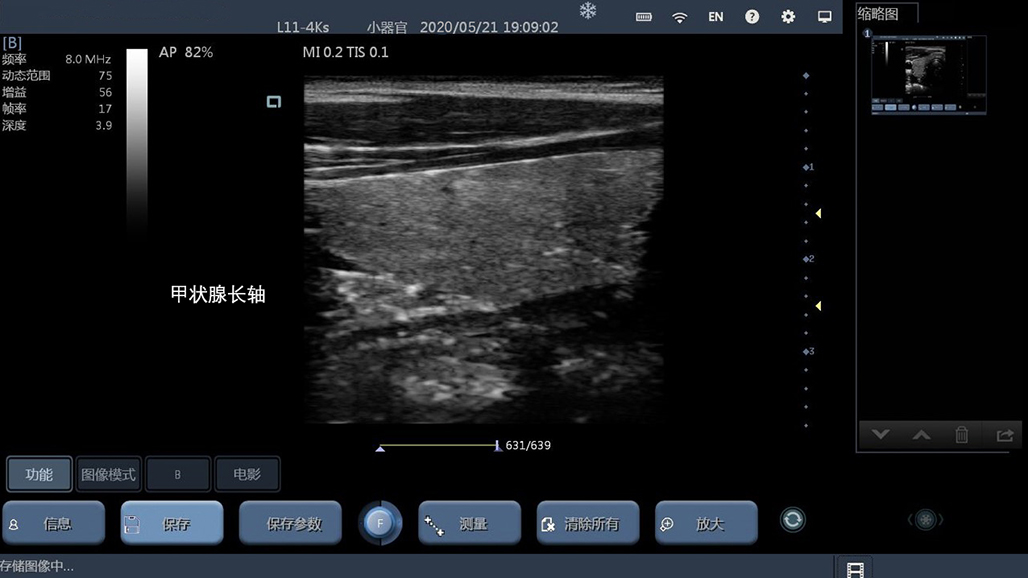

• 线阵

甲状腺